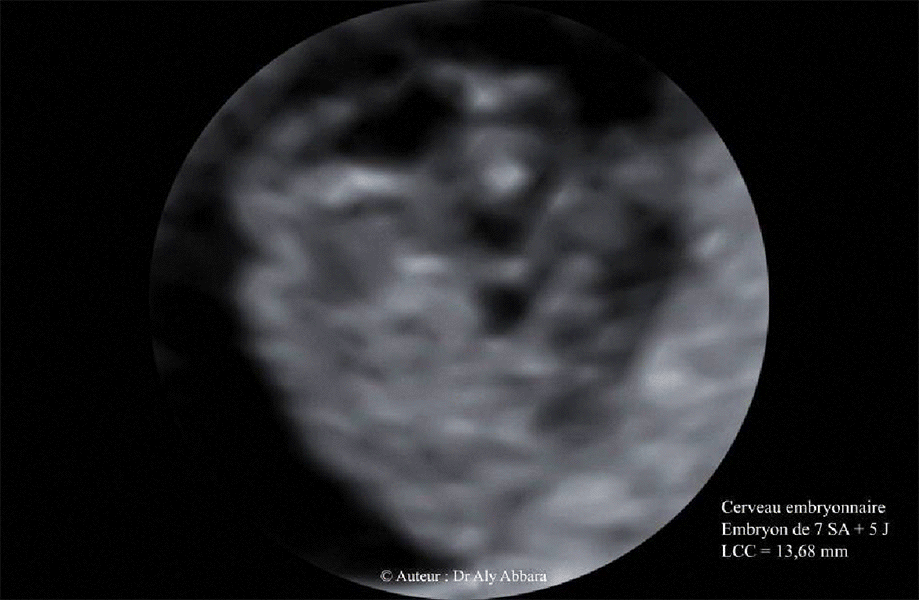

Cerveau embryonnaire - embryon âgé de 7 SA + 5 jours

(LCC = 13,68 mm)

Coupe sagittale médiane :

Analyse des éléments formant de l'ensemble du cerveau à cet âge embryonnaire : le prosencéphale avec sa vésicule (futur 3° ventricule) ; le mésencéphale et sa vésicule (futur aqueduc cérébral) ; le rhombencéphalique avec sa vésicule (futur 4° ventricule) ; la courbure mésencéphalique.